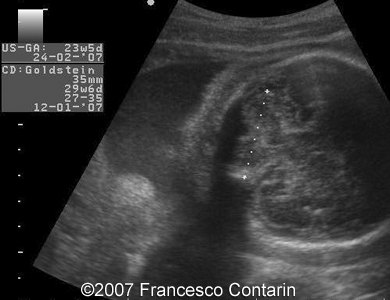

This is a 22-year-old woman (G4, P2) with unremarkable familiar history, referred to our hospital at 29 weeks of gestation due to a fetal ascites. There were no signs of maternal-fetal blood incompatibility. The ultrasound investigation revealed rhizomelia, postaxial polydactyly, small thorax, short ribs, ascites, increased abdominal biometric parameters, polyhydramnios. We supposed two diagnoses: Short rib-polydactyly syndrome versus Jeune syndrome (asphyxiating thoracic dystrophy).

Images 1, 2. 29th week of pregnancy -  shortened femur (left); and ulna (right).

Images 3, 4. 29th week of pregnancy -  shortened tibia (left); and polydactyly of the hand (right).